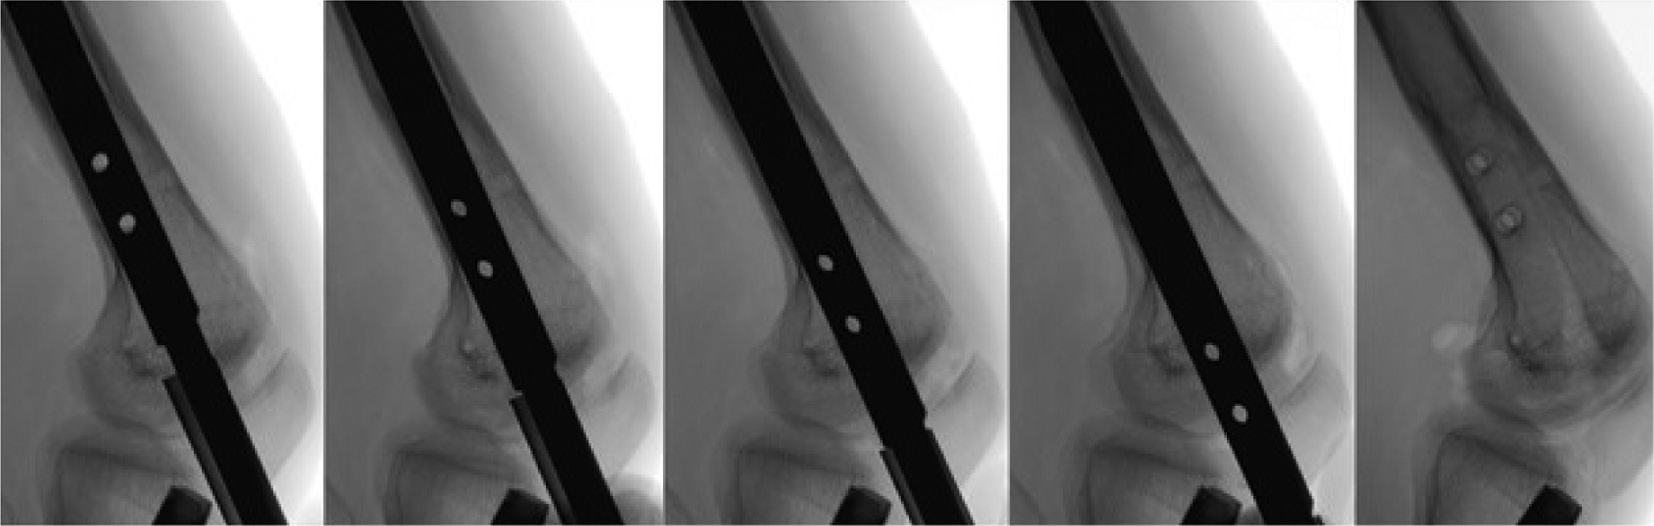

Figure 7a (left) and 7b (right). Carefully advance the guidewire under fluoroscopic guidance into the center of the nail on the anteroposterior view (7a) and the lateral view (7b).

jposna20220031_fig7.jpg

Figure 8. Tap the guidewire with a mallet into the proximal end of the nail. If one looks carefully, they can see heterotopic bone over the proximal end of the nail. Reaming the muscle and bone over the nail will develop a clear path for threading in the extraction bolt.

jposna20220031_fig8.jpg